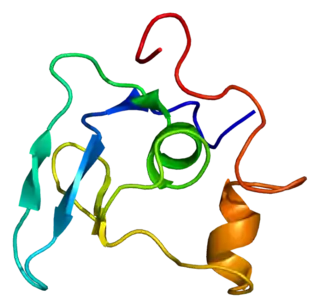

Fibrilina

La fibrilina es una glucoproteína, esencial para la formación de las fibras elásticas del tejido conectivo.

La fibrilina-1 es el mayor componente de las microfibrillas que constituyen un armazón sobre la cual se deposita la elastina. Las microfibrillas se componen de punta a punta de polímeros de fibrilina. Hasta el momento, se han descrito tres formas de fibrilina.

La proteína fibrilina-1 fue aislada por Sakai, 1986, y las mutaciones en el gen han sido vinculados con el síndrome de Marfan. Al presente más de 100 diferentes mutaciones se han descrito.

La proteína fibrilina-2 fue aislada en 1994 por Zhang, y se piensa que juega un papel en la temprana elastogénesis. Las mutaciones en el gen de la fibrilina-2 han sido enlazados con la aracnodactilia (que es también un síntoma clínico del síndrome de Marfan). Más recientemente, la fibrilina-3 fue analizada y se cree que se localiza mayormente en el cerebro. Además de en el cerebro, la fibrilina 1 se localiza en las gónadas y ovarios de los ratones de campo.

Tanto la fibrilina-1 como la fibrilina-2 están codificados por dos diferentes genes, FBN1 y FBN2, localizados en los cromosomas humanos 15 y 5, respectivamente. Una mutación en el locus FBN1 podría causar el síndrome de Marfan.